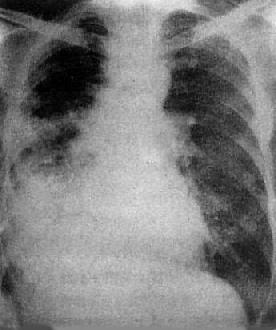

图3-1-28 右上叶支气管肺癌(中心型)

A.后前位B.前后位体层像右上叶密度均匀增高,下缘清楚、上突,

与肺门肿块影形成似横置S状。体层像示肿块突入右支气管腔内